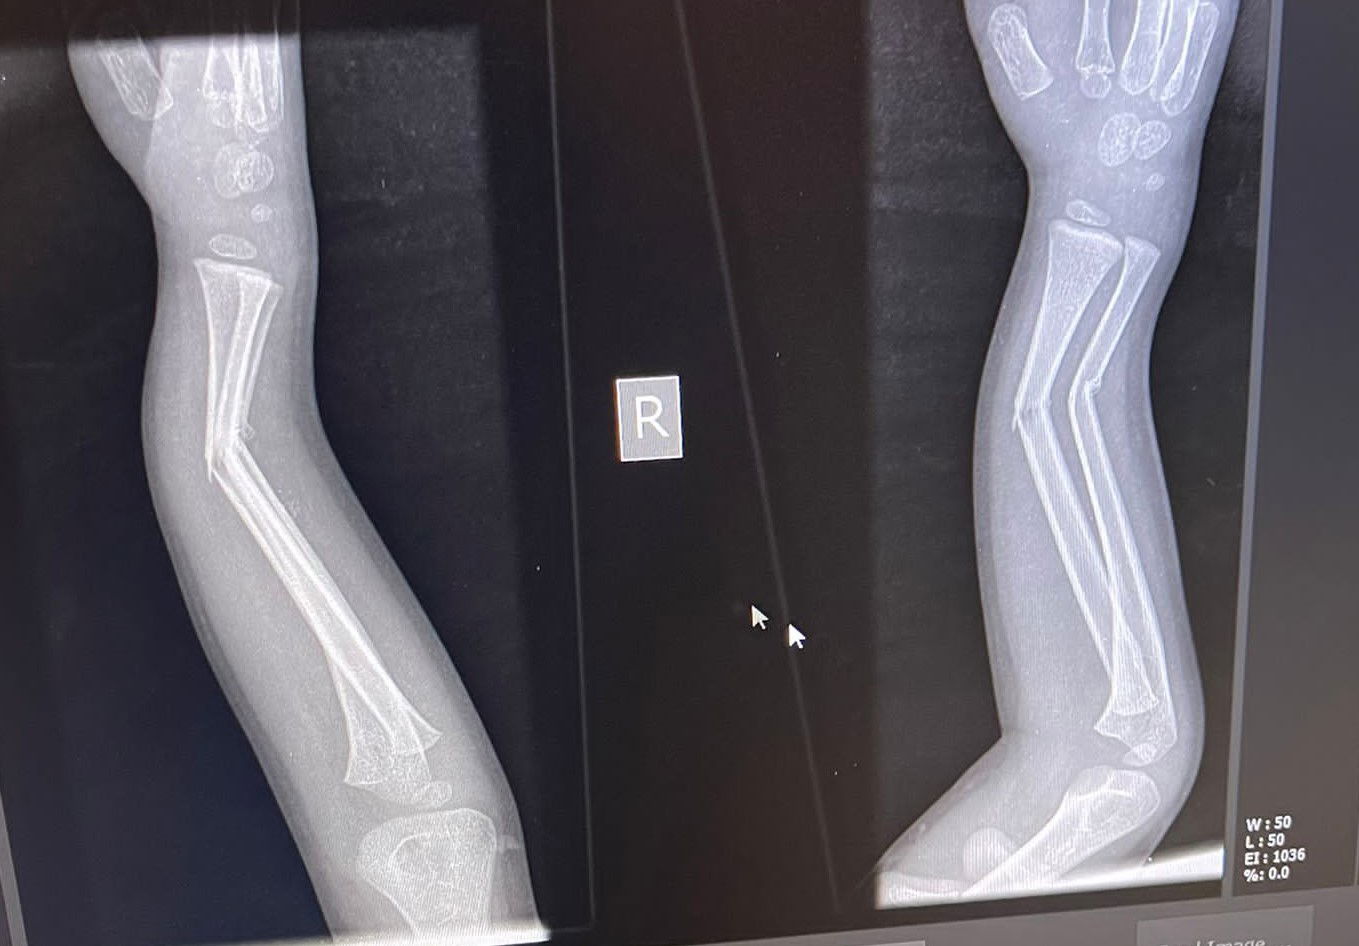

הקיץ החל ועמו תאונות האופניים. בשבוע שעבר הובא למיון 'טרם' במודיעין עילית פעוט בן 4.5, כשהוא סובל מפציעה המצריכה ניתוח דחוף. מוחמד פרוך, אח מוסמך במיון טרם, סיפר כי "לדברי ההורים, הילד נתקע עם אופניו בחוזקה בקיר. הילד נראה כאוב מאוד וניכר כי הוא סובל מפציעה באמה. בצילום רנטגן ניכר בברור שהוא שבר את עצמות האמה בשני מקומות".

"הענקנו לו טיפול רפואי, במשככי כאבים, וגיבסנו את האמה כדי להקל על הכאבים עד לניתוח. הילד הופנה בדחיפות לניתוח".